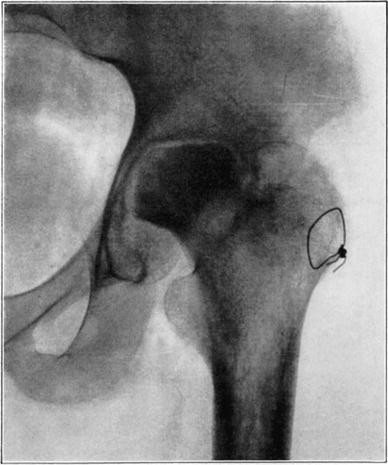

Case 2. Seventy-four days after fracture of neck of astragalus, posterior dislocation of body, and reduction by operation. Body necrotic and retained normal density. Atrophy of disuse of other bones. Bony union of fracture.

Case 2. One hundred and sixty days after fracture. Body slightly reduced in density near fracture due to invasion from neck.

Case 3. Fresh fracture of neck of astragalus and chip off superior and posterior portion of os calcis.

Case 3. Two hundred and seventy-four days after injury. Fracture of astragalus united. Superior and posterior part of body broken down and irregular while remaining portion dense and transformed. Indicative of necrosis of body with secondary changes.